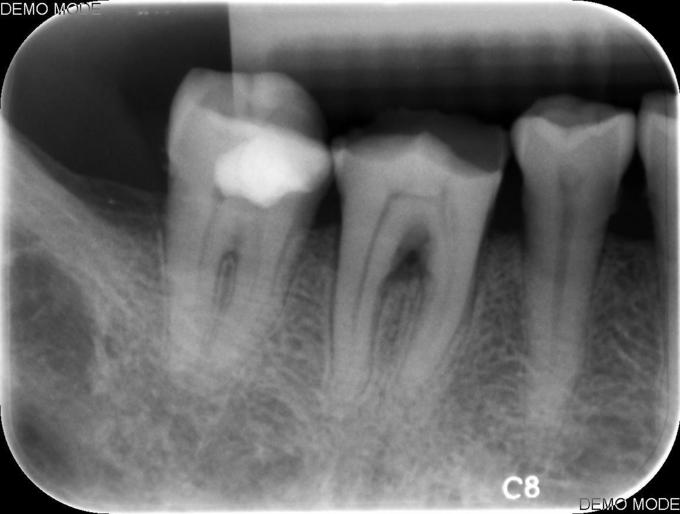

主诉:牙冠变色3年余,要求修复,于修复科转诊 现病史:患者3年前开始出现牙冠变色,无自发痛、夜间痛,无冷热刺激痛,欲改变牙体颜色,于我院就诊,咨询后修复科转诊行根管治疗。 既往史:无特殊

检查:#47牙体变色,见he面缺损,叩(+-),松(-),冷热测无反应,电测无反应,牙龈正常无红肿。#48缺失。 X线:未见明显异常。

诊断:牙髓坏死 治疗#47碧兰麻下开髓,封三甲+OC球,ZOE暂封,嘱2周后复诊,不适随诊。 去暂封,清理髓腔及根管,双氧水和生理盐水交替冲洗,测WL,拍片试尖达工作长度,根管内导入糊剂,侧压充填中下段,热牙胶充填上段,X线示恰填,树脂充填修复。